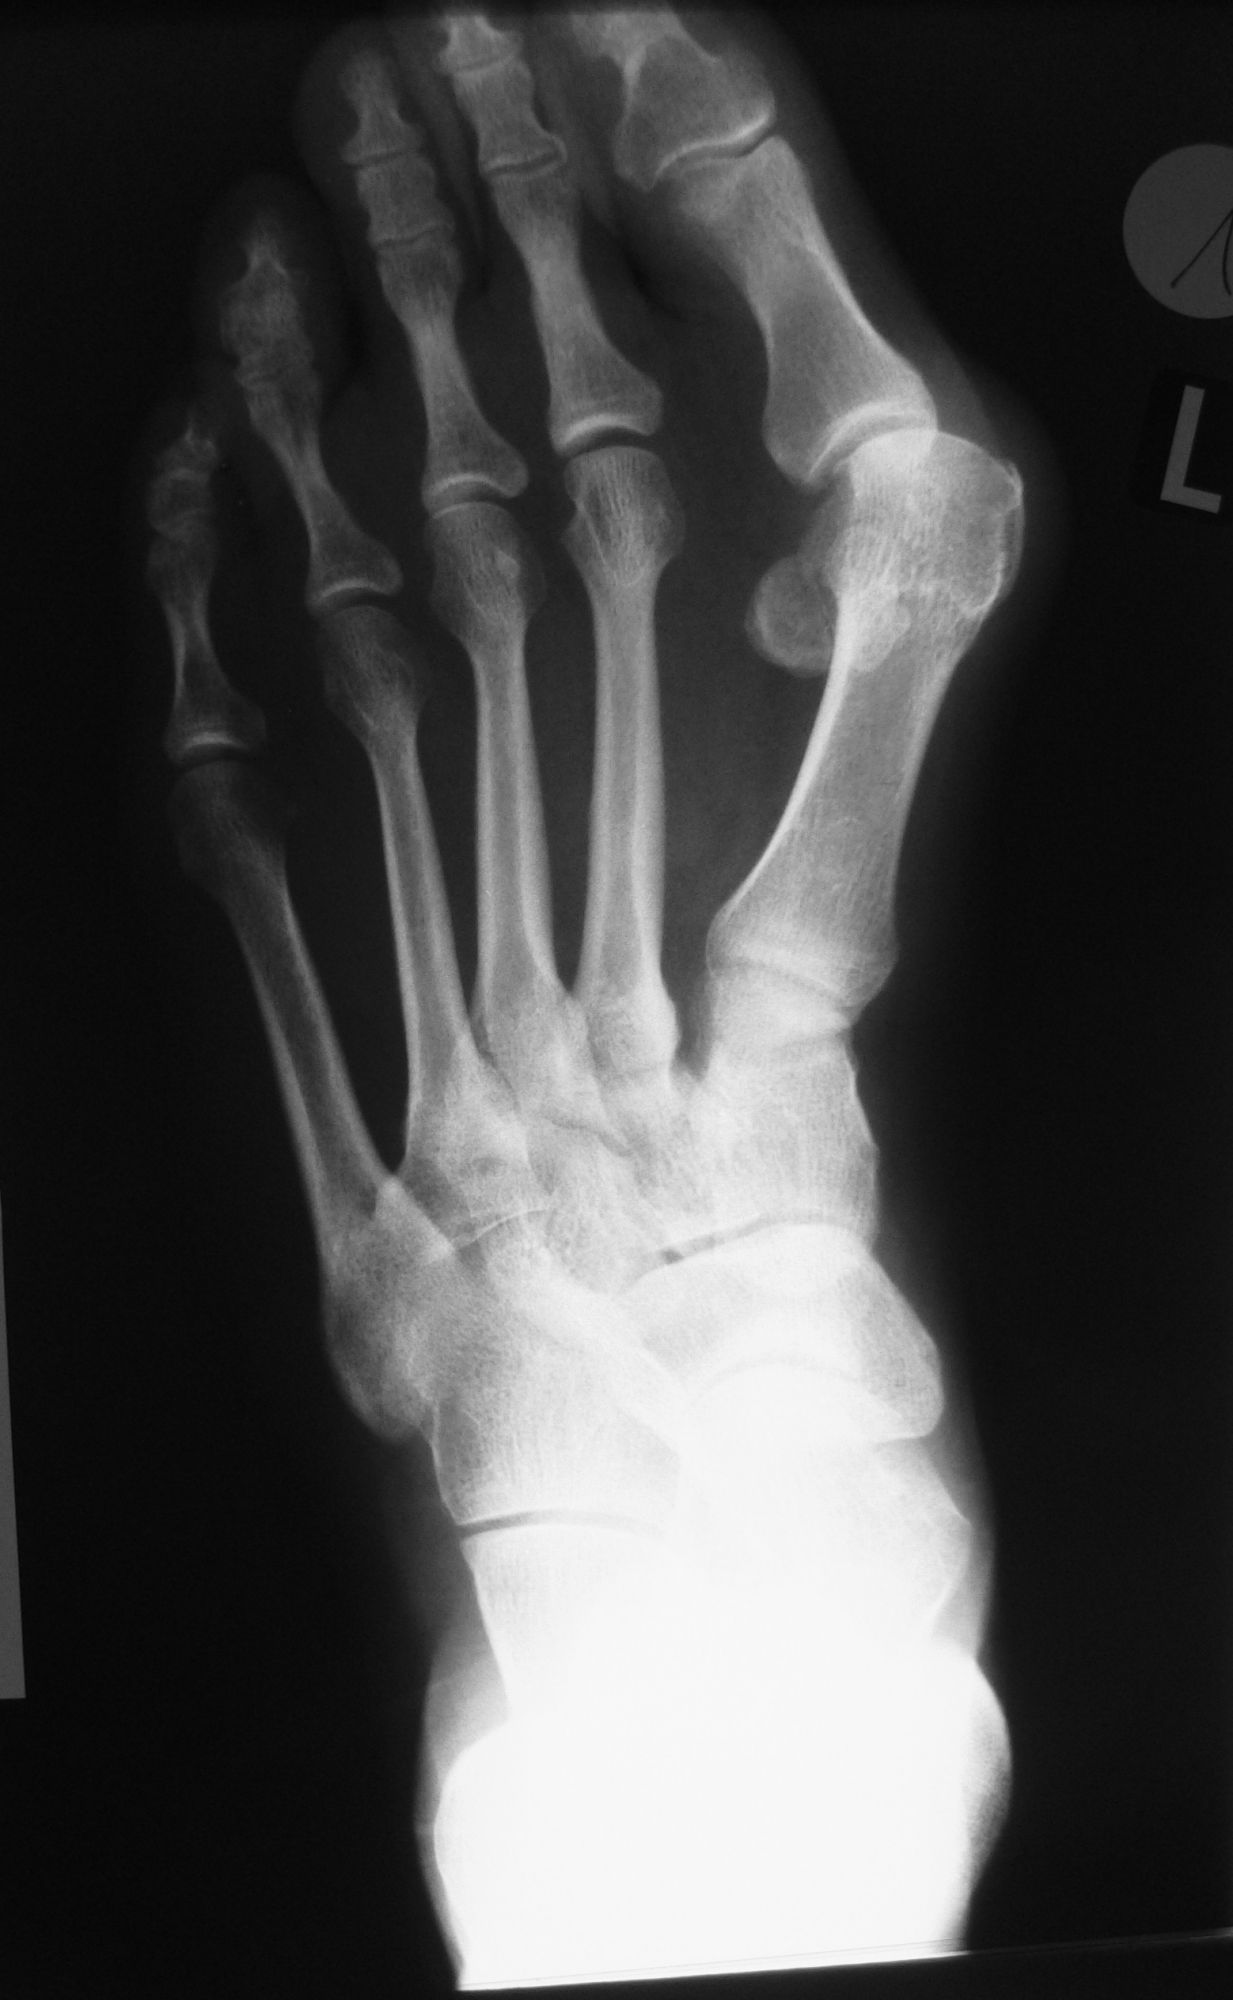

Röntgenaufnahme des Fußes (unter Belastung) in dorsoplantarem, seitlichen und schrägem Strahlengang (Abb. 1a-c).

Beurteilung des ersten Intermetatarsalwinkels (IMA), des Hallux valgus Winkels (HVA), des distalen (Distal Metatarsal Articular Angle, DMAA) und proximalen Gelenkflächenwinkels der Grundphalanx (Proximal Phalangeal Articular Angle, PPAA). Möglicherweise muss die Arthrodese des TMT-1-Gelenks mit weiteren distalen Eingriffen zur Korrektur des Gelenkwinkels kombiniert werden (z.B.: retrokapitale Osteotomie oder Grundphalanxosteotomie).

Zur Vollansicht bitte die Bilder anklicken.

Abbildung 1a

Abbildung 1b

Abbildung 1c